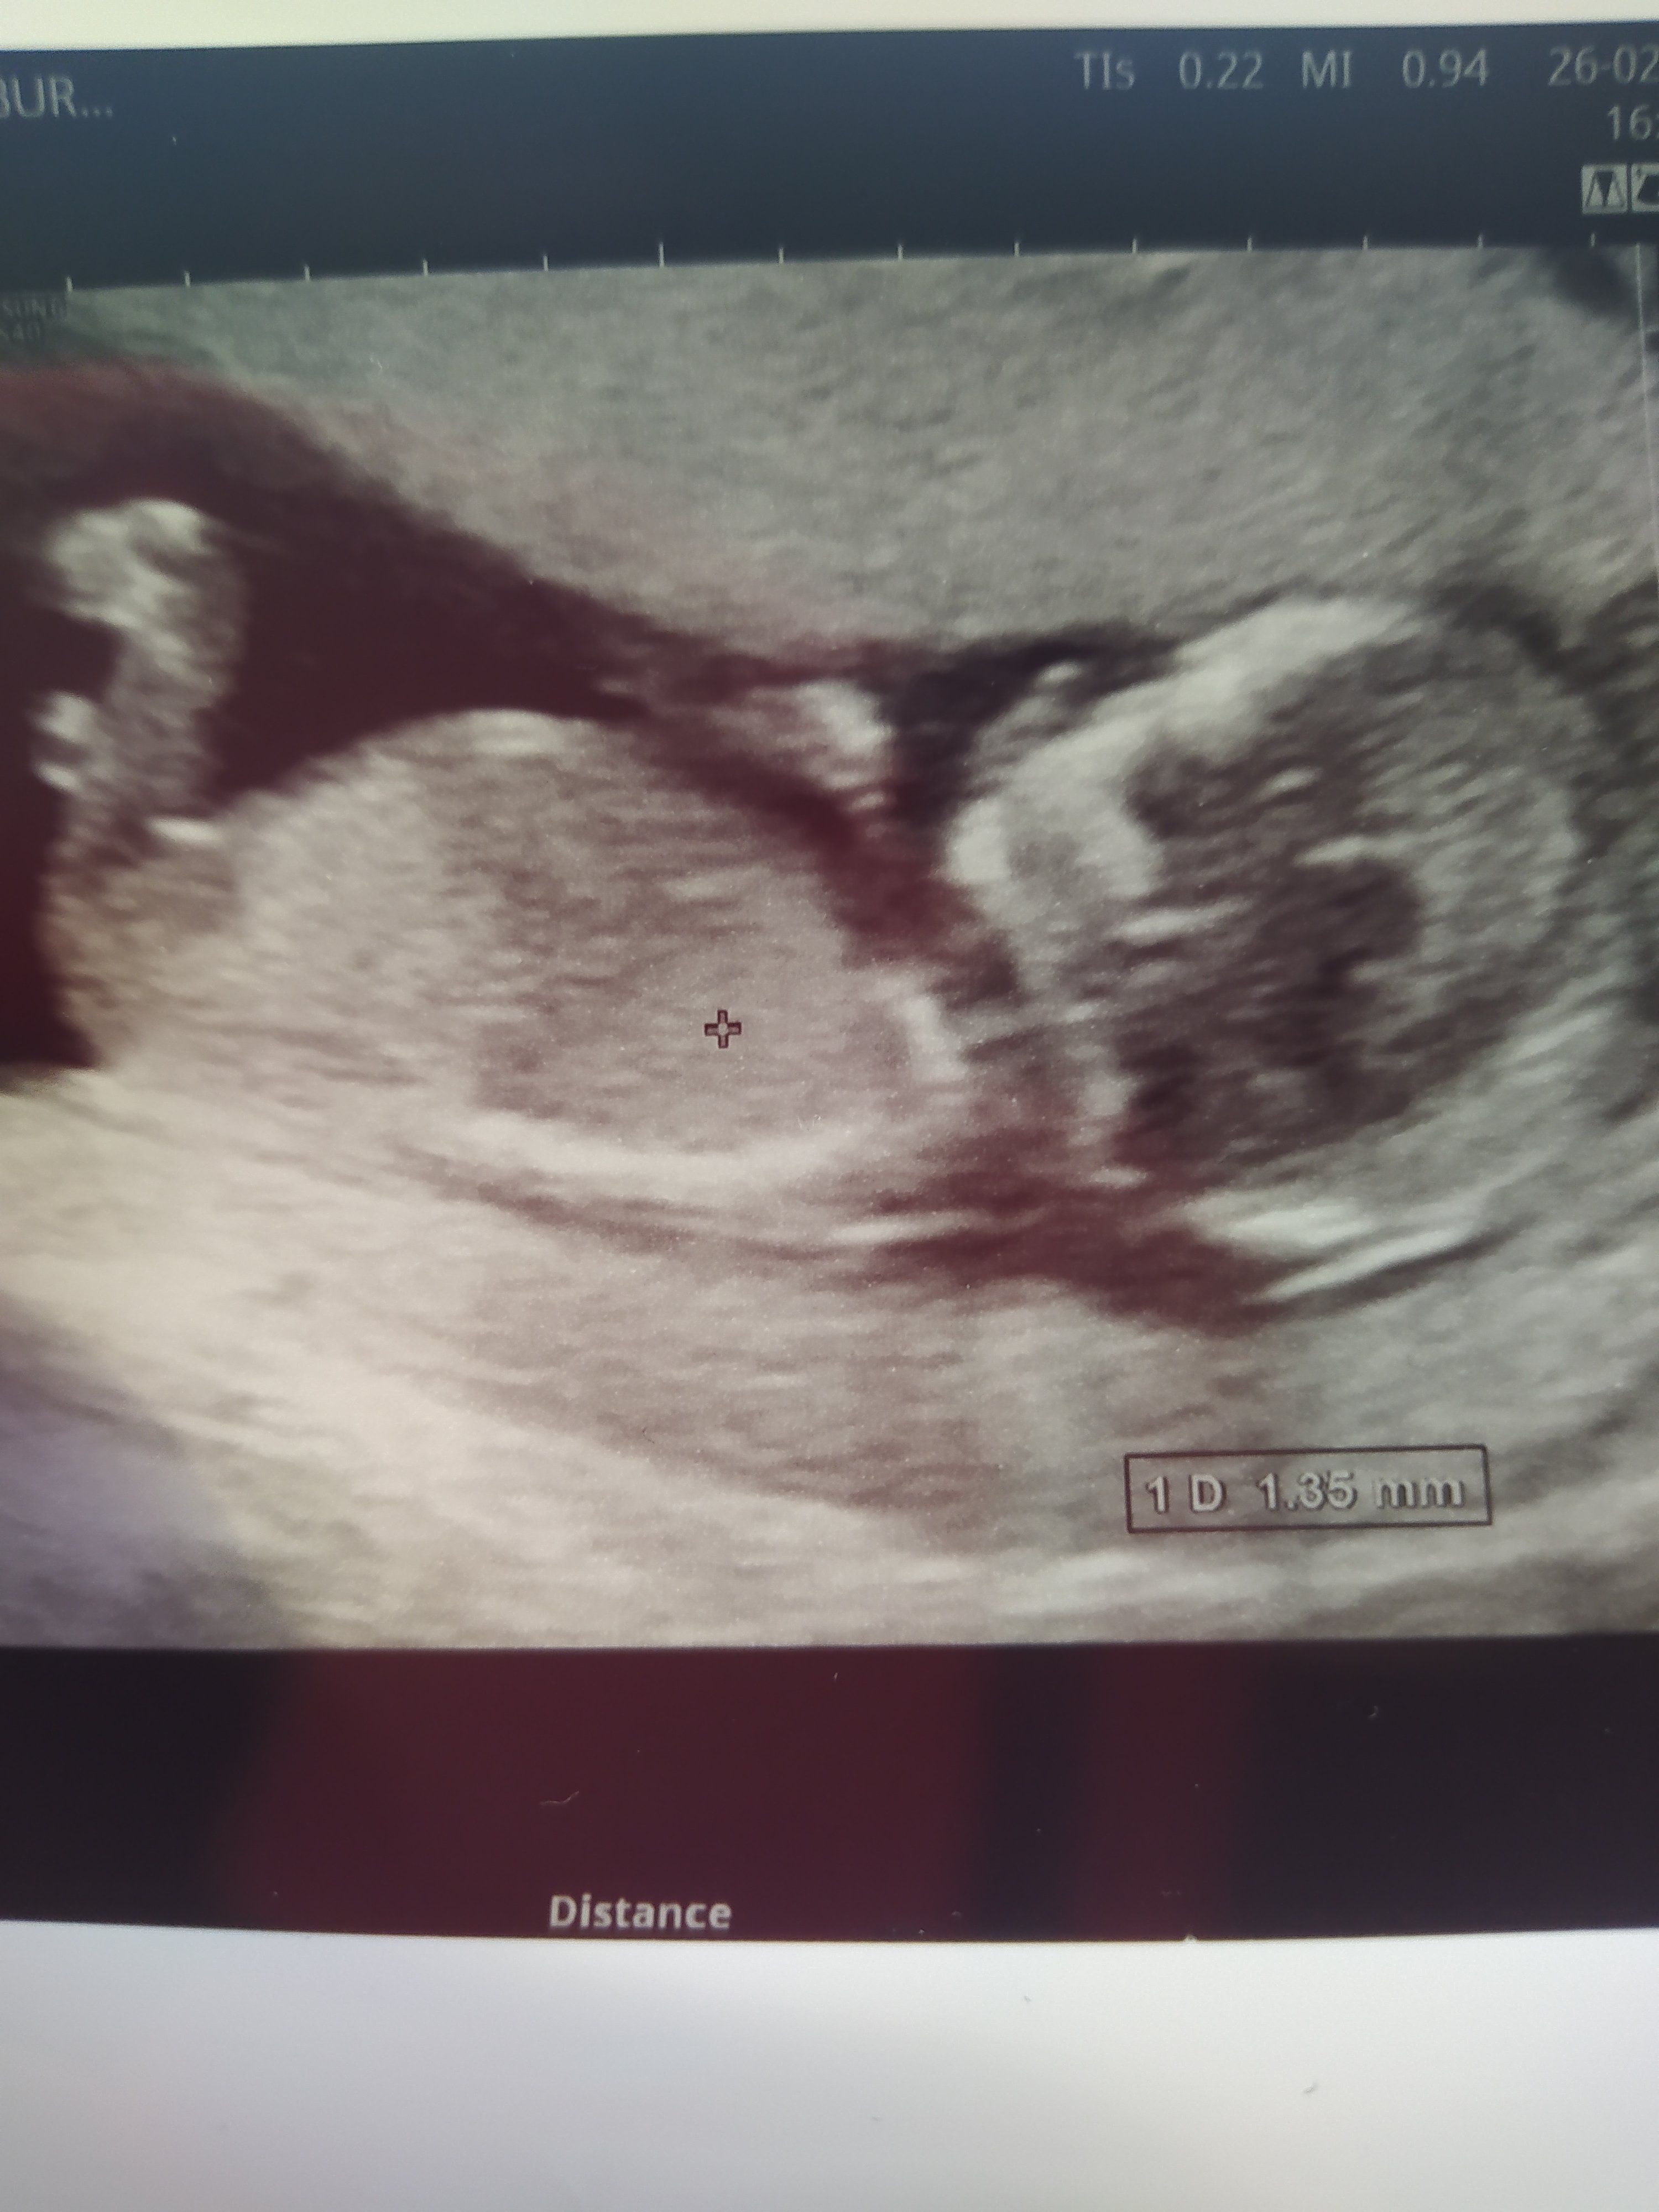

Rüzgar gülü canım baktım inceledim ama çok flu çekilmiş gorseller daha net olanı yok mu ya da daha net çekebilsen daha iyi yorumlayabiliriz

Selamlar Sevgili Nermin, Resmi baya inceledim ama görmemiz gereken genital tüberkülül görünmüyor dolayısı ile bir cinsiyet tahmini malesef yapamıyorum. Başka resim var ise yükleyin onlara da bakalım olur mu ?